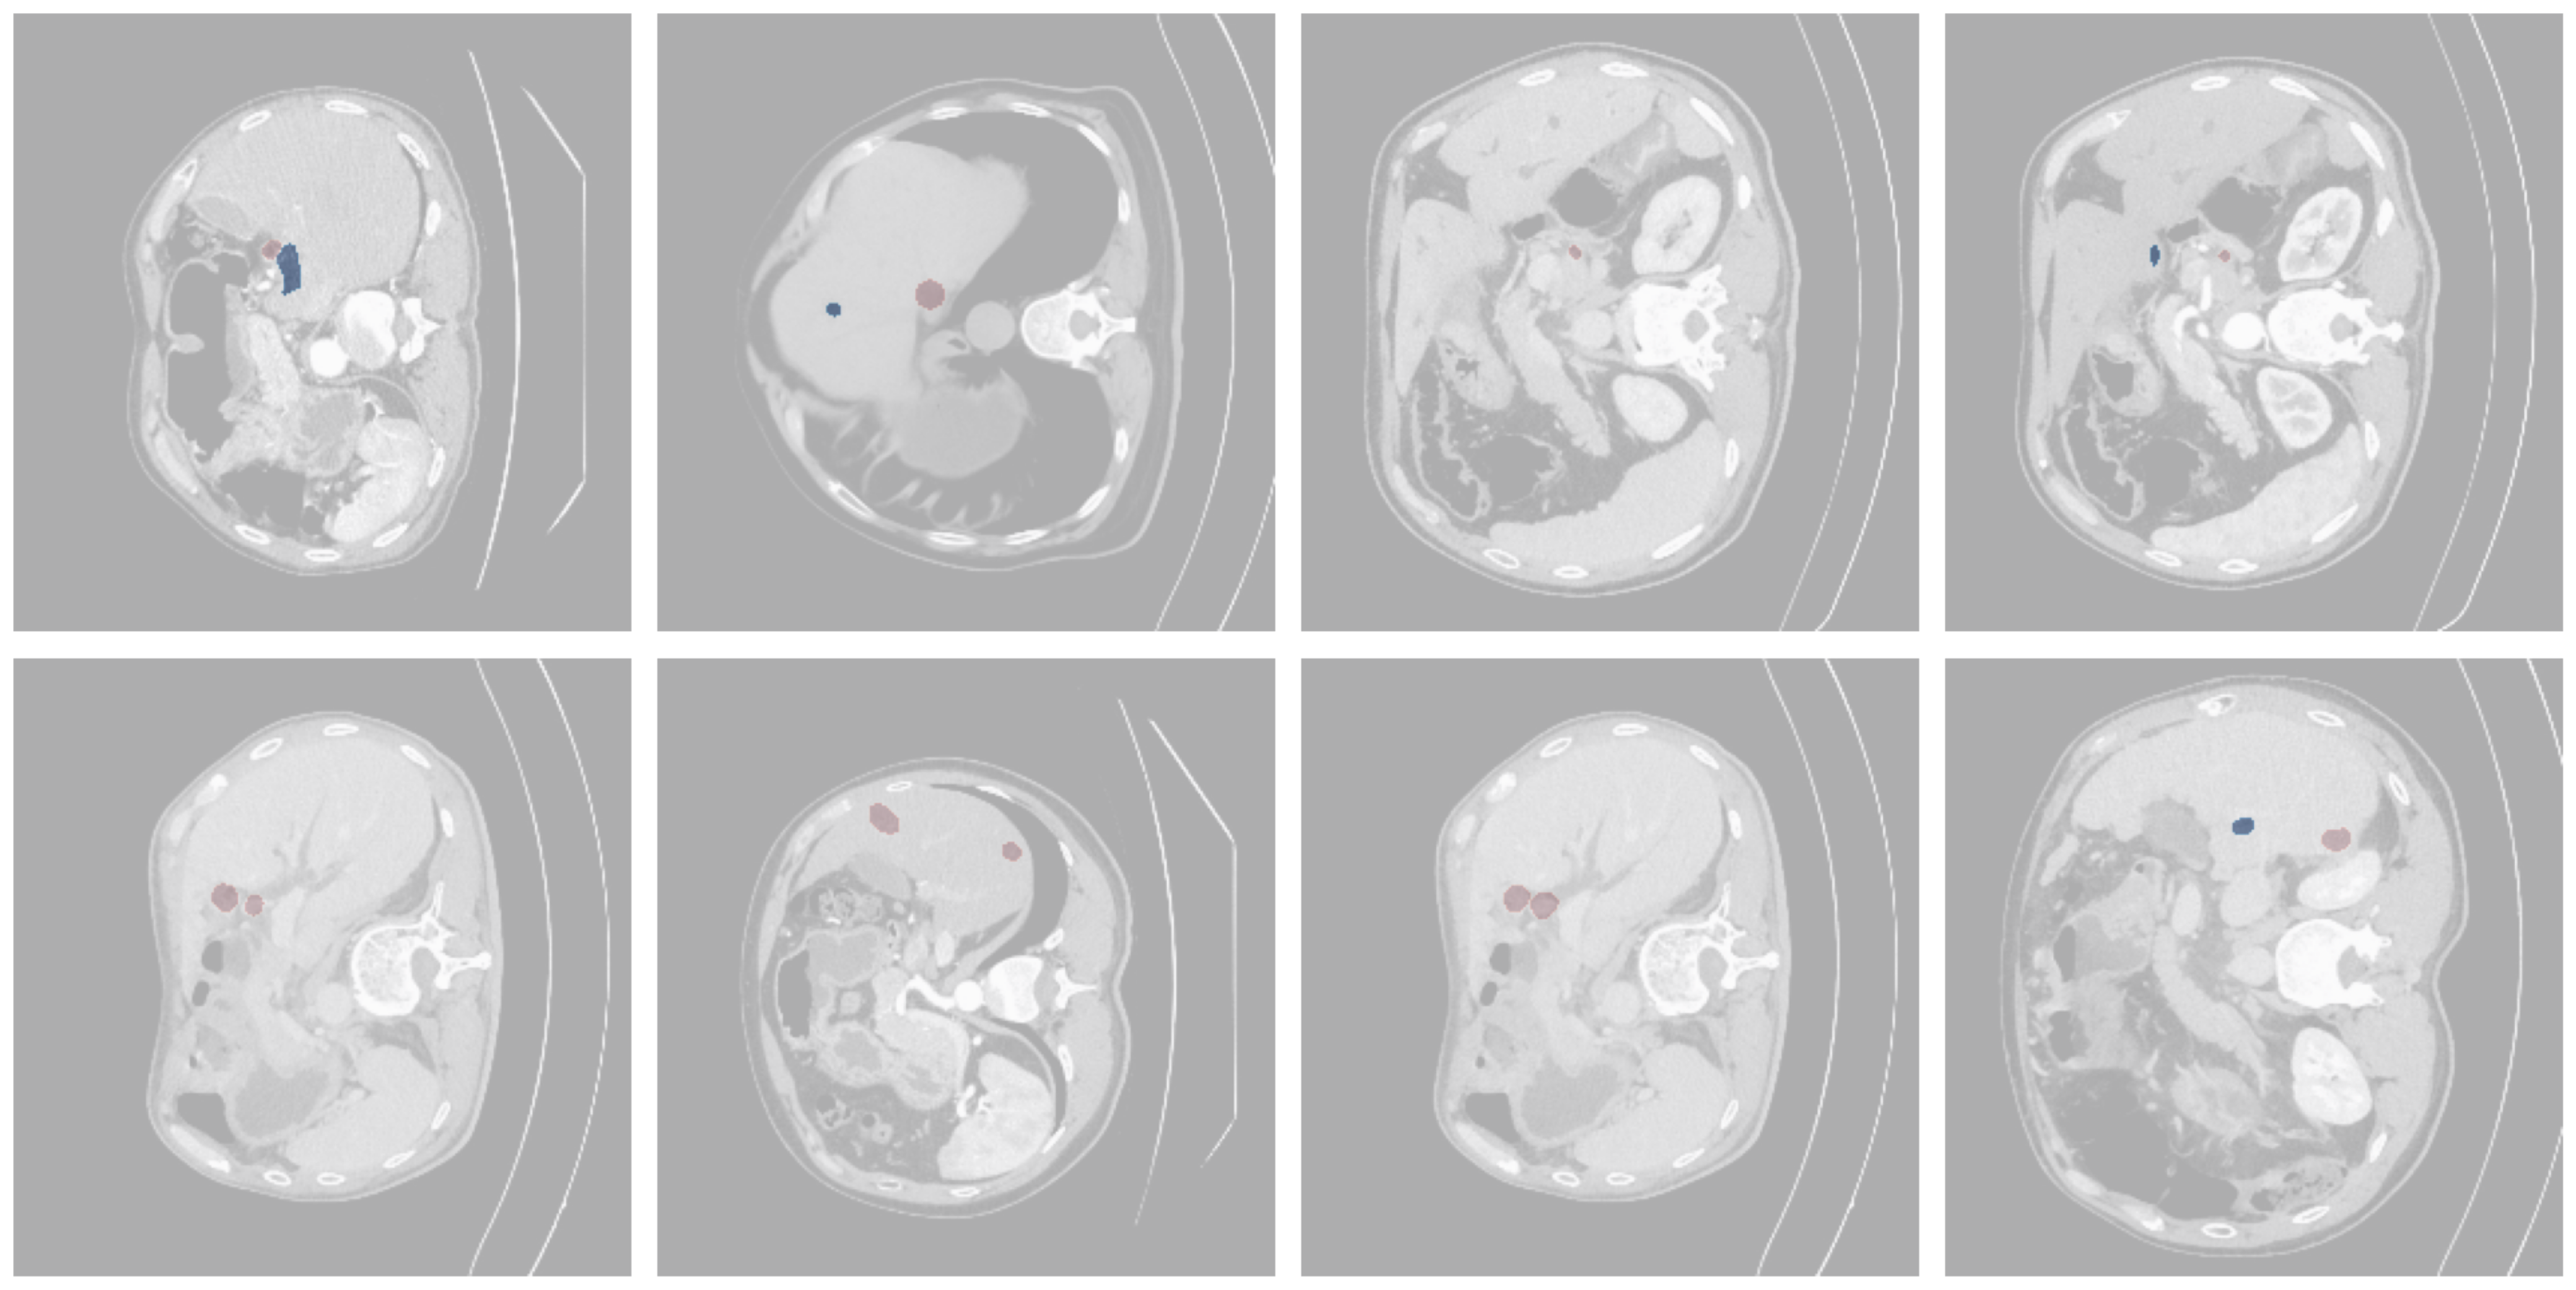

Refer to caption

Figure 6: The visual comparison of seven segmentation methods against ground truth on the testing set. The predicted and GT are highlighted in blue and red, respectively.

Predicted masks from the best-performing model, ResNetUNet3+, show more accurate tumor boundary delineation and fewer false positives compared to other architectures. Example cases illustrate both successful segmentations and challenging scenarios, such as small lesions or lesions adjacent to vessels, where performance remained limited. Visual comparisons highlight that ResNetUNet3+ with medium size of parameters (31.1 million) is more robust in capturing tumors than baseline UNet or Mamba- and Transformer-based alternatives as shown in Fig. 6.